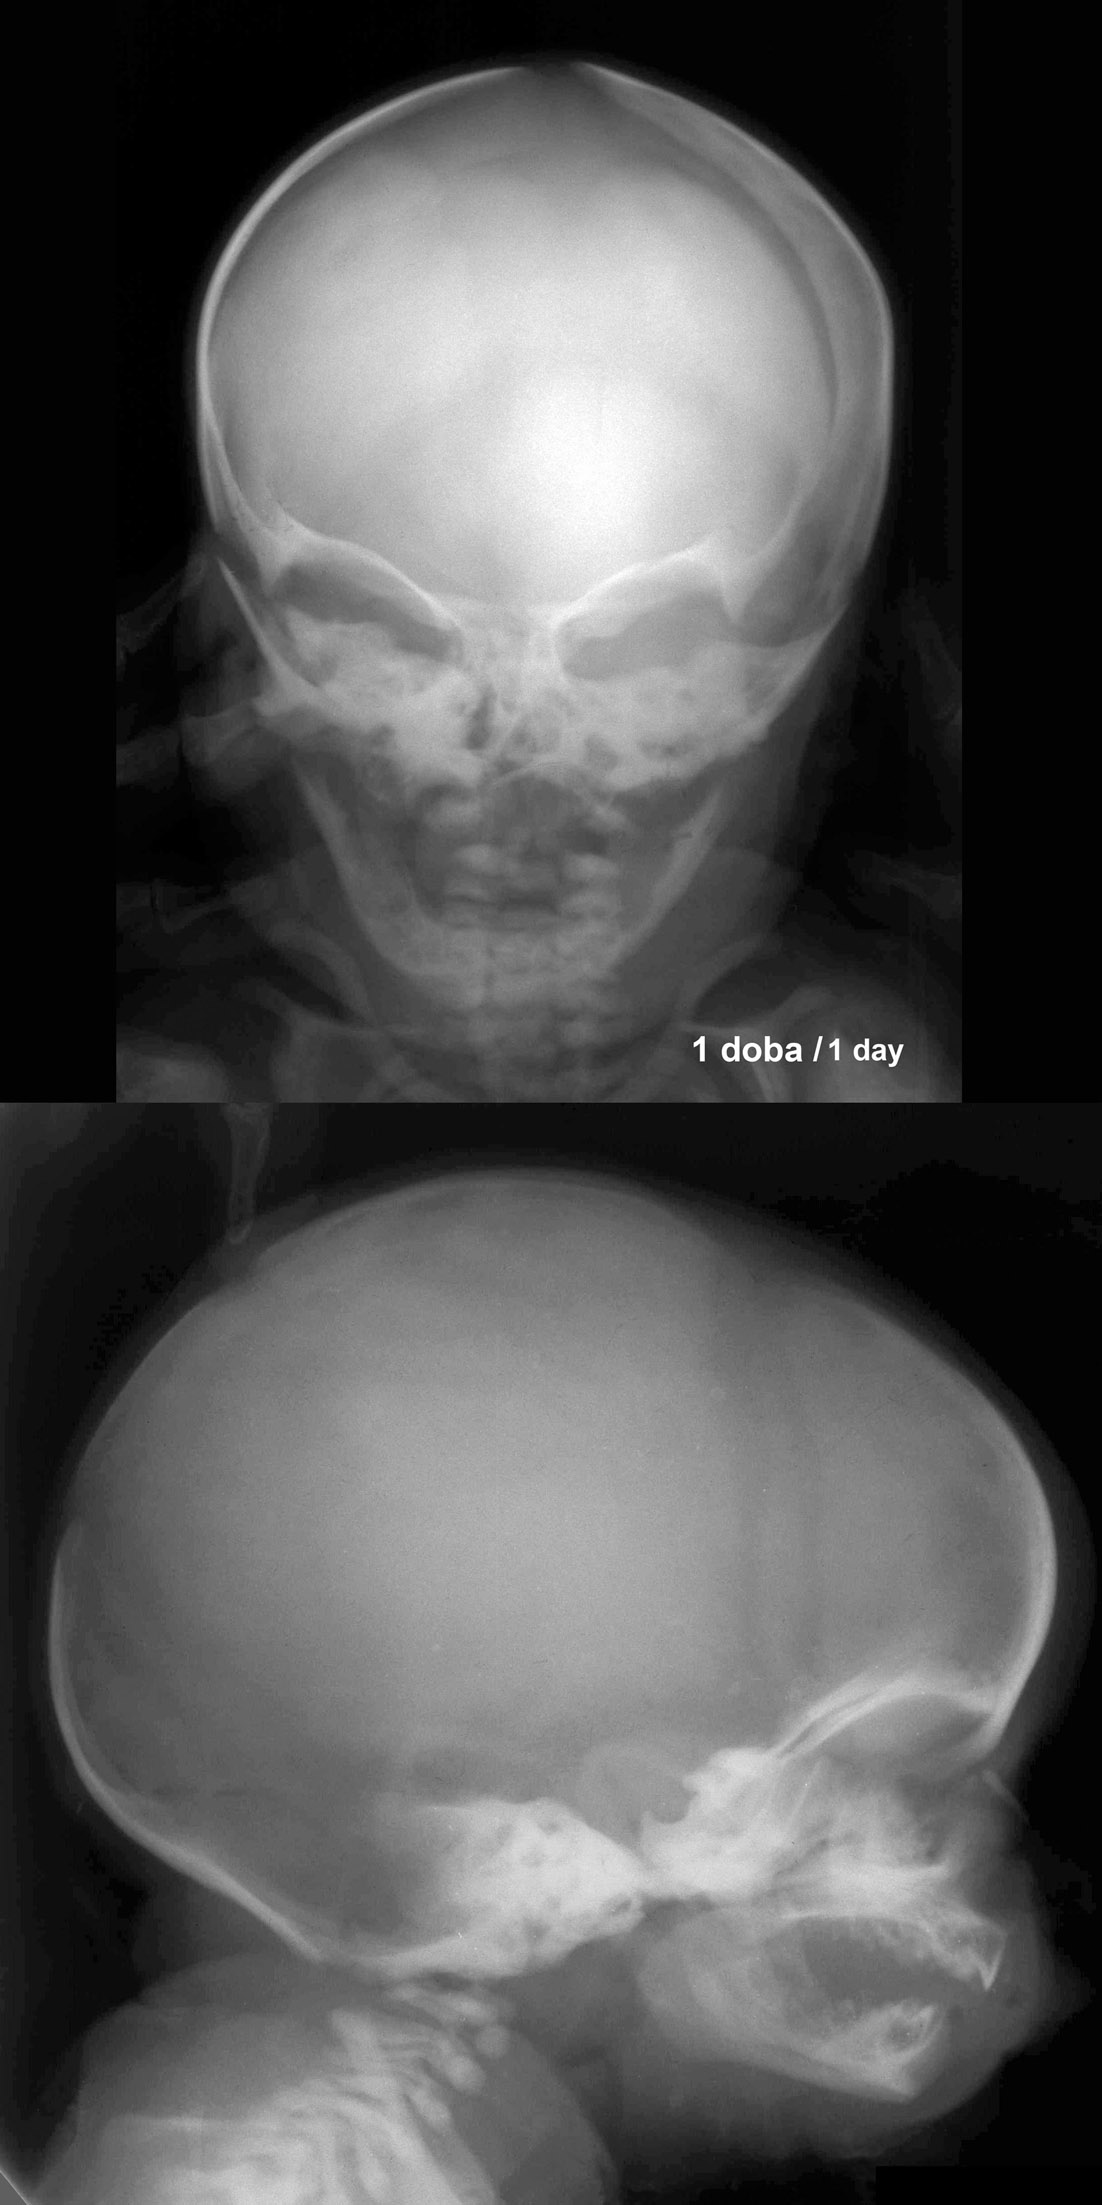

RTG głowy 1 dzień po porodzie.

RTG głowy 6-miesięcznego dziecka.